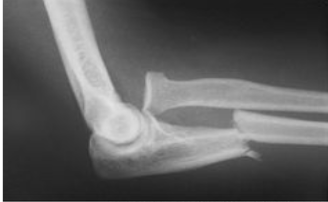

What type of fracture is this?

Monteggia

What is a monteggia fracture?

Fx of proximal half of ulna with dislocation of radial head

May happen if raise arms to block blows to the head